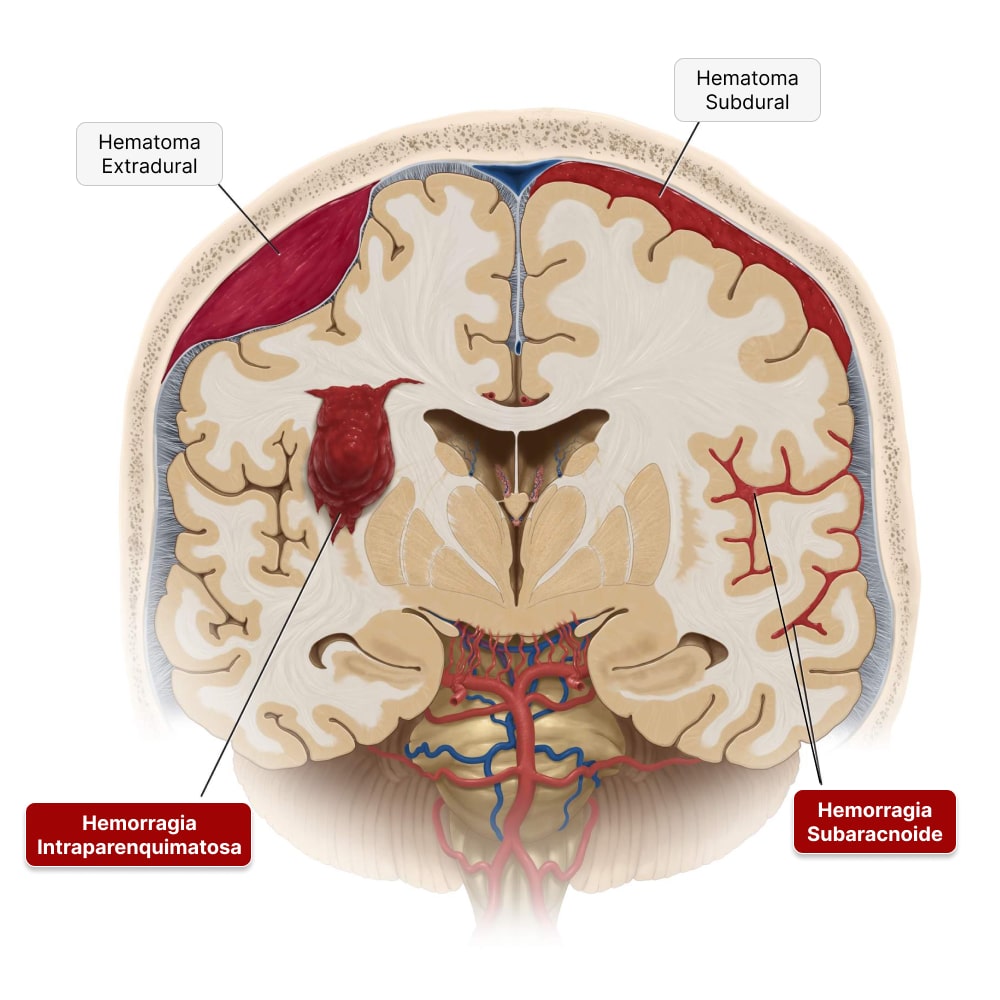

Dependendo da localização do sangue, o AVC hemorrágico (AVCH) pode ser dividido em dois tipos diferentes:

- Hemorragia intraparenquimatosa ou hemorragia intracerebral: é o tipo mais frequente de AVC hemorrágico, que acontece quando o extravasamento de sangue ocorre no meio do cérebro, formando um hematoma que aumenta a pressão intracraniana e afeta a função das áreas cerebrais vizinhas. É principalmente sobre esse tipo que falaremos neste artigo.

- Hemorragia subaracnóide: nesse tipo de AVC hemorrágico, a hemorragia acontece entre o cérebro e as meninges (membranas que o recobrem). A causa mais importante de hemorragia subaracnóide é o rompimento de aneurismas cerebrais. Já falamos sobre ela em outro artigo que você pode ler aqui.